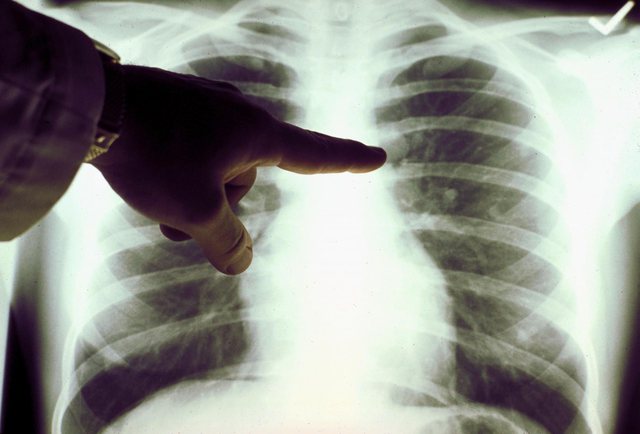

Megjithatë, kur ajo vendosi më në fund që të bënte një skaner të gjoksit, kanceri ishte gjëja e fundit që mund t’i shkonte ndërmend. Skaneri zbuloi një masë në mushkërinë e djathë që rezultoi të ishte tumor malinj. Rivas nuk kishte pirë asnjëherë sikur edhe një cigare të vetme në jetën e saj.

Kanceri i mushkërisë është më i përhapuri në të gjithë botën dhe çdo vit vret më shumë gra se kanceri i gjirit, vezores dhe mitrës të kombinuar së bashku. Nëse diagnostikohet herët, sëmundja kurohet lehtë, si në rastin e Rivas, e cila ka arritur ta luftojë këtë sëmundje vdekjeprurëse. Por, vetëm 16% e rasteve kapen që në fazën e parë. Zakonisht është si një gjëndër 7-8 milimetra e vendosur në mes të mushkërisë, që nuk shfaq asnjë simptomë. Shumë pacientë diagnostikohen vetëm kur tumori është përhapur shumë dhe po shkakton probleme me frymëmarrjen.